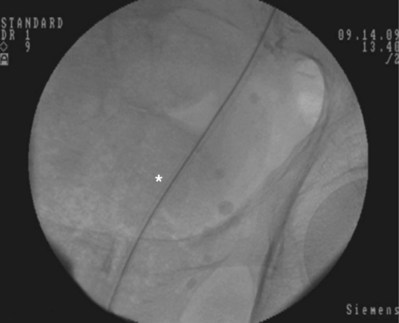

An alternative technique that relies more on fluoroscopic visualization for stent placement and less on cystoscopic visualization is often advantageous when dealing with more challenging stent placements such as impacted ureteral stones or malignant obstruction (Figs. 7-7 through 7-16).

Figure 7–13 A metal tip pusher is used to advance the stent to the desired position. Asterisk shows the pushers radiopaque marker.

After obtaining bladder access with either a flexible or rigid cystoscope, a floppy-tip guidewire is advanced into the ureteral meatus and coiled in the renal pelvis using fluoroscopy, the cystoscope is then removed and an 8- to 10-Fr coaxial dilator is advanced under fluoroscopy until the 10-Fr sheath is at the urethral meatus. The 8-Fr internal dilator is removed, leaving a conduit (10-Fr outer sheath) through which to advance the stent.

The ureteral stent is then advanced over the guidewire through the 10-Fr sheath by using a pusher with a small fluoroscopically visible metal band at its tip. The metal tip pusher is advanced under fluoroscopic control to the upper border of the pubic symphysis in male patients and lower border in female patients, while stabilizing the position of the lower end of the stent. The 10-Fr sheath and subsequently the guidewire are removed, allowing the stent to curl in the bladder.